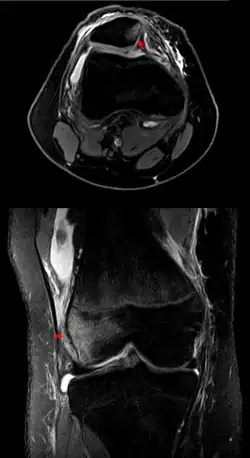

In jedem Fall muss – falls dies nicht von selbst geschehen ist – die Kniescheibe eingerenkt werden. Hierbei sollte unter Anleitung des Arztes oder eines erfahrenen Sporttrainers das Knie langsam und vorsichtig wieder gestreckt werden, wobei die Kniescheibe fest mit der Hand geführt wird, damit sie nicht unvermittelt überspringt. Wenn die Kniescheibe vorsichtig in die Ausgangsposition geführt wird, kann diese ohne Begleitverletzung der Gelenkflächen wieder reponiert werden. Dabei sollte es nicht zu einem heftigen Einschnappen kommen, was einen Knorpelschaden verursachen kann. Der Betroffene merkt nach der Reposition eine deutliche Schmerzlinderung. Nach der Reposition sollte das Knie geröntgt werden und eine Kernspintomographie erfolgen, um die richtige Lage der Kniescheibe zu kontrollieren und um Begleitverletzungen auszuschließen.